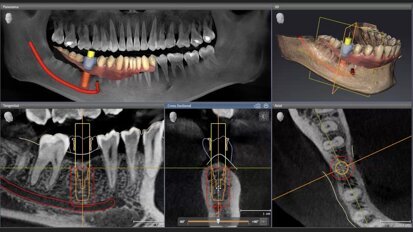

Un dispositivo que ofrece previsibilidad del tratamiento en implantología y cirugía oral

Los responsables del desarrollo del nuevo motor quirúrgico Implantmed Plus II, Isabella Schmied, Gerente de Producto de Cirugía Oral, y Andreas ...